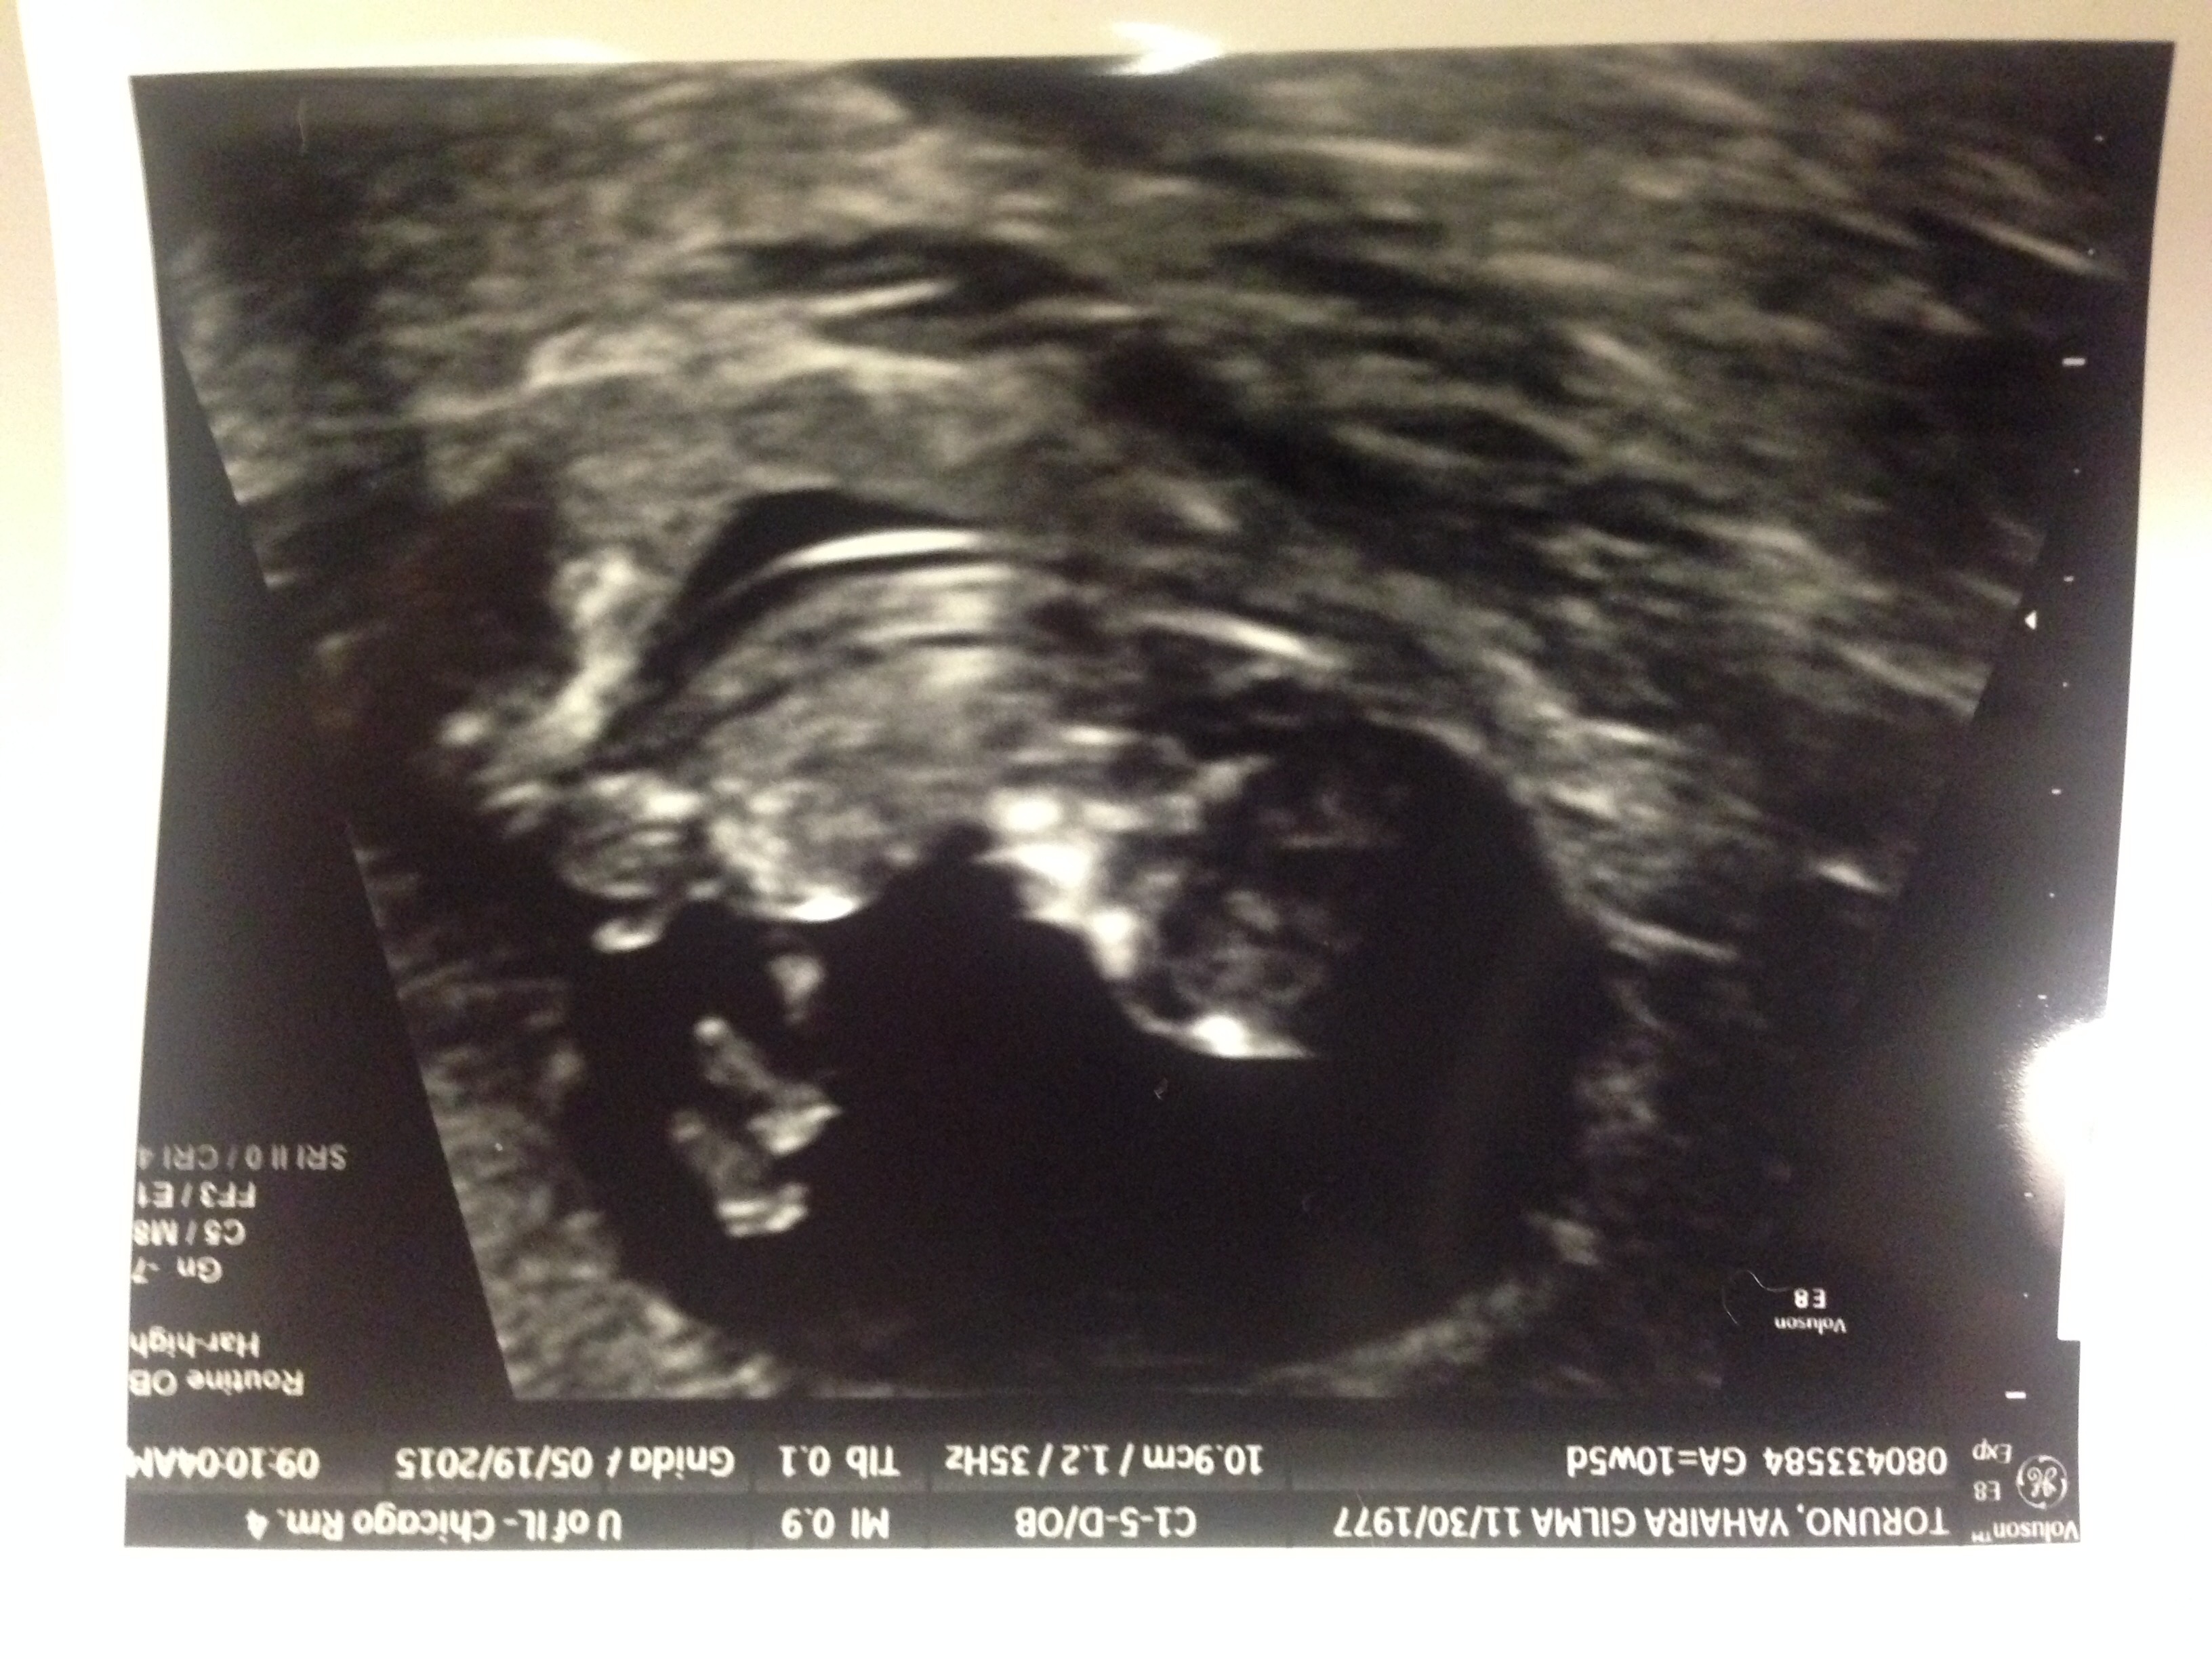

I thought I was 9 weeks today but am actually measuring at 8 weeks 3 days. My OB decided to keep the original due date since it's less than a week difference. Christmas Eve baby!